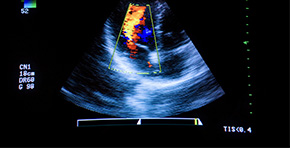

Ultraschall

Die inneren Organe der Brust- und Bauchhöhle, kleine Strukturen wie die Schilddrüse oder in der Haut befindliche Knoten können mittels Ultraschall bildhaft dargestellt und beurteilt werden. Wir führen auch die ultraschallgeführte Feinnadelbiopsie durch. In der Kardiologie wird das Herz in der Bewegung dargestellt und eine Blutstrommessung mit Doppler vorgenommen. So wird eine exakte Diagnose gestellt, um eine passende Therapie einzuleiten. Bei der Geburtsüberwachung dient er zur Beurteilung der Herzfunktion der Föten.